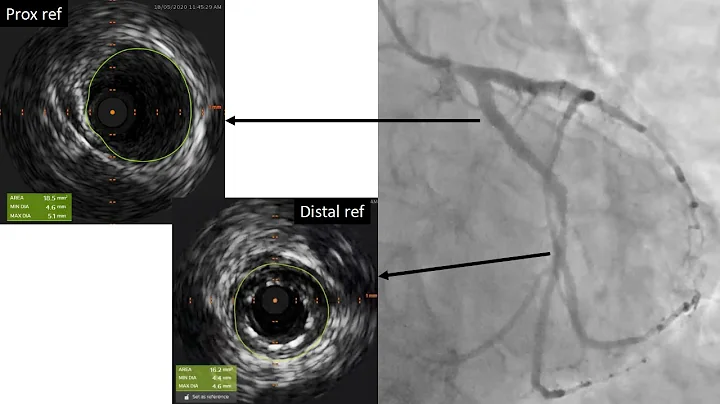

Ivus-guided Pci To Lcx